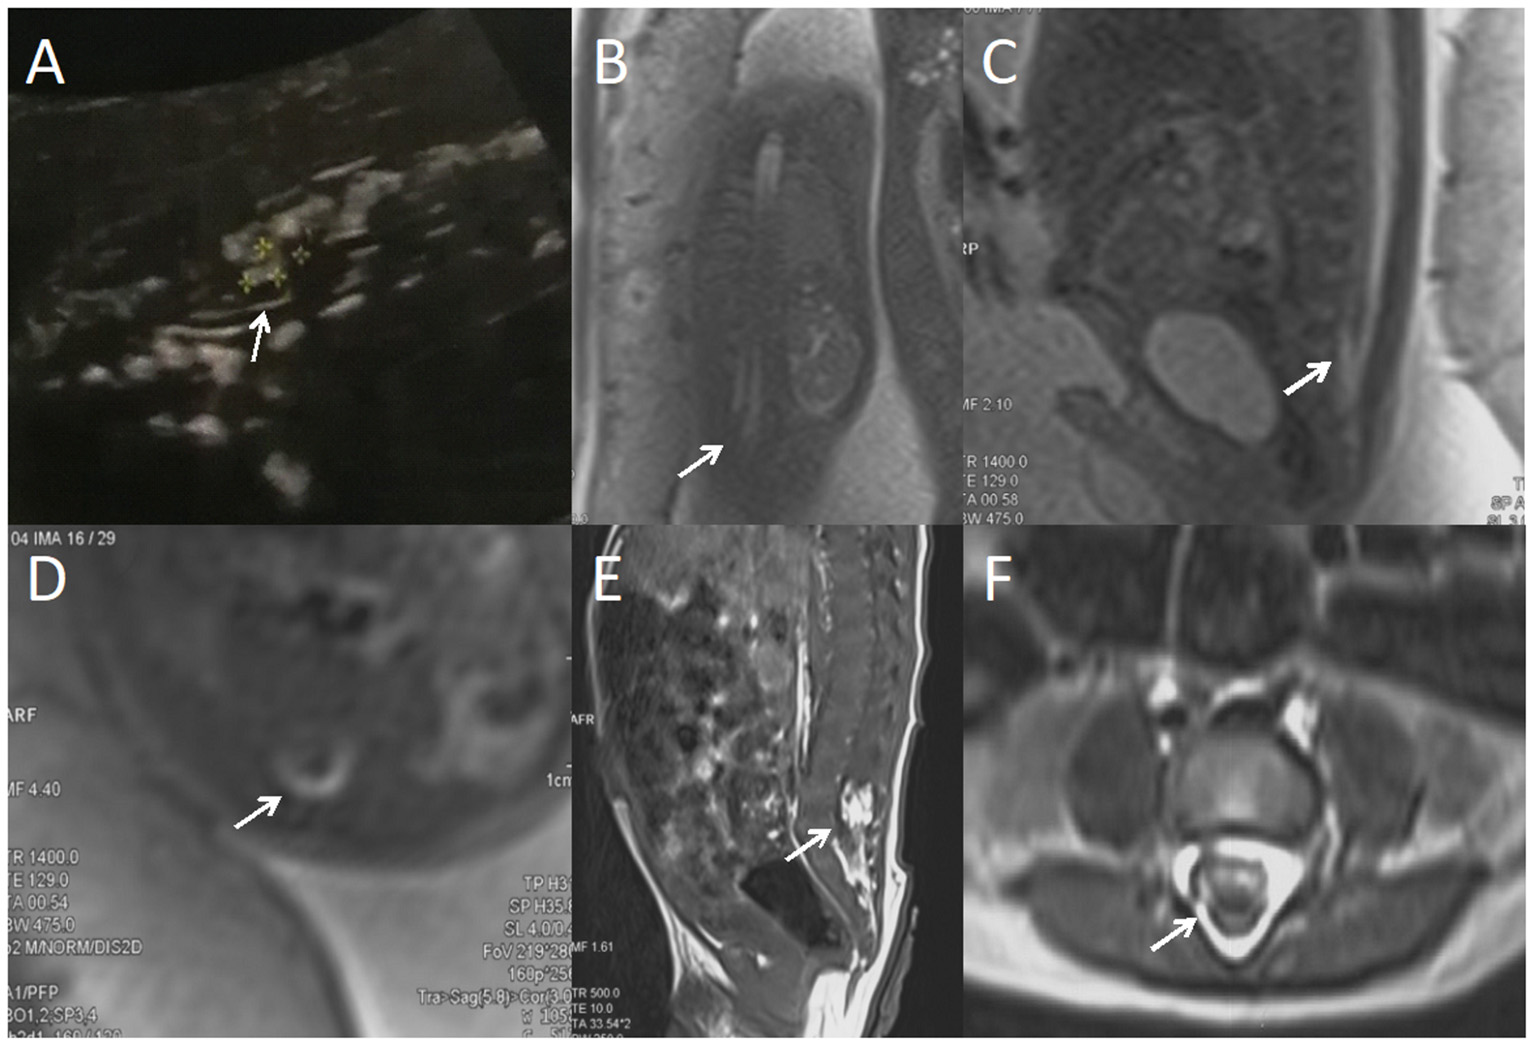

Figure 1

A fetus with intraspinal lipoma. (A) the prenatal ultrasound examination at 24 weeks of gestation showed the presence of low conus medullosus in the fetus, hyperechoic mass shadow in the spinal canal, and broken spinal continuity. Thus, spina bifida and intraspinal lipoma were considered. (B) Fetal magnetic resonance imaging (MRI) examination at 24 + 2 weeks of gestation showed a coronal view of the low conus medullosus of the fetus, with enlarged end of the conus medullosus and tight adhesion to the posterior edge of the spinal canal. (C) Sagittal view showed the low conus of fetal myeloma cord. (D) In the axial position, normal subarachnoid space in the spinal canal disappeared, with lipoma and spinal nerves mixed. (E) T1 sagittal MRI of the lumbosacral vertebrae 10 days after birth suggested intraspinal lipoma. (F) Axial MRI of the lumbosacral vertebrae showed uneven internal signal of lipoma, which was considered to be a hybrid lipoma with the spinal nerves.